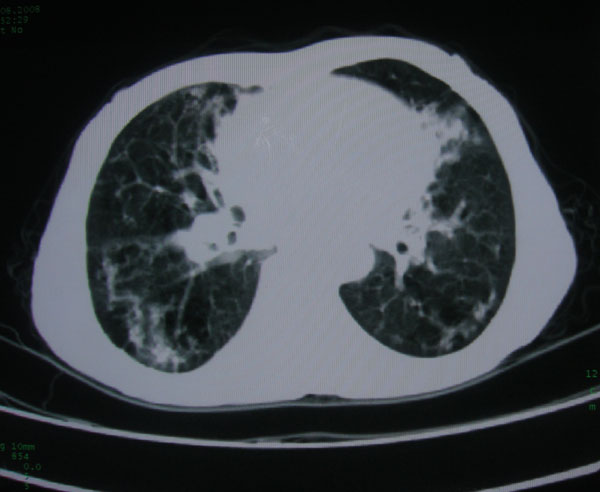

标题: CT15046:F59Y,咳嗽间断咳血丝痰就诊. [打印本页]

咳嗽\间断咳血丝痰就诊.

考虑支气管扩张并感染

本例应该是“慢性疾病并发多种合并症”即:慢支并感染并支气管扩张征!结合病灶分布 形态分析,不除外合并“继发性肺结核”!

慢性支气管炎伴全小型肺气肿、支气管扩张、感染、间质纤维化。

慢性支气管炎伴全小叶型肺气肿、支气管扩张、感染、间质纤维化